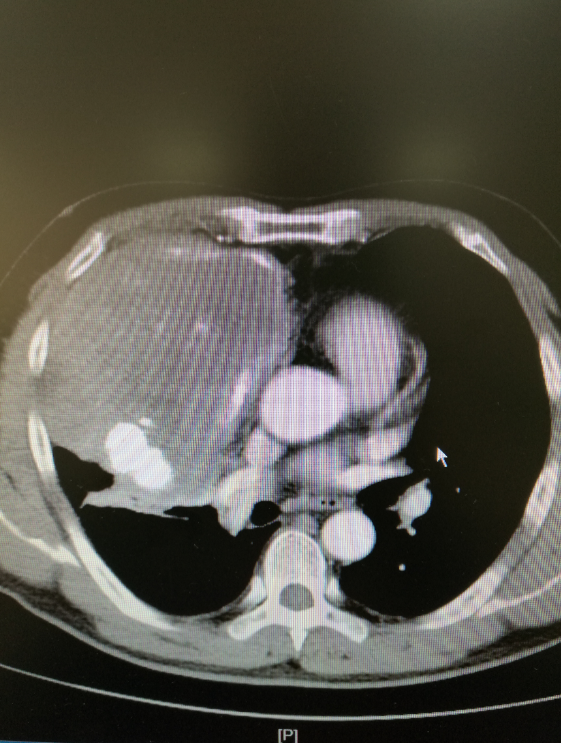

巨大肿瘤已经压迫心脏,大血管,导致病人纵隔向左移位来胸科医院就医之